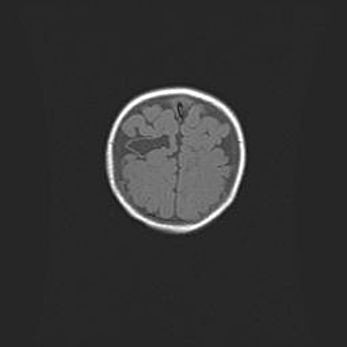

Церебральная ишемия II.

Возраст: 5 дней

Вес: 3400 г

Пол: женский

Окружность головы: 35 см

Срок гестации: 39 недель

Церебральная ишемия – это заболевание, характеризующееся недостаточностью (гипоксией) либо полным прекращением (аноксией) снабжения мозга кислородом по причине закупорки одного или нескольких сосудов. Это приводит к  что метаболическим расстройствам различной степени тяжести в тканях головного мозга, развитию коагуляционных некрозов и гибели нейронов.